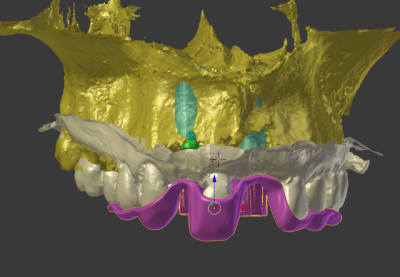

toujours avec mon nouveau jouet, je n'avais jamais testé mais cela fonctionne parfaitement bien

plus besoin de faire couler le plâtre par le labo!!!

un scan ou un cone beam de l'empreinte suffit

très simple ensuite de préparer une provisoire